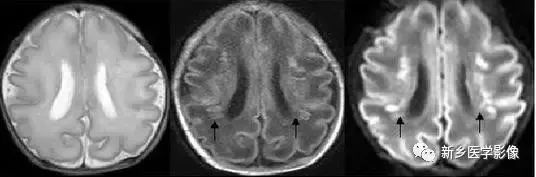

5.脑室周围白质软化症

主要与缺血缺氧及感染有关.常见于早产儿.是造成早产儿脑瘫的主要原因。由于脑室周围白质的血供分别来自脑室区和远脑室区的终动脉。未成熟儿终动脉深穿支的侧支循环尚未建立,而胚胎晚期脑室周围白质对缺血缺氧敏感。所以,脑室周围自质软化症多见于早产儿。由于病灶常为双侧性,故双侧侧脑室多同时扩大。脑白质内软化灶在CT扫描时表现为白质内斑片状低密度灶.MR T1加权图呈低信号,T2加权图呈高信号。

6.脑室周围白质软化症

主要与缺血缺氧及感染有关。

常见于早产儿。常见于早产儿的原因与胚胎期脑部损害发生的时间有关,胚胎早中期脑损害主要引发发育畸形,晚期主要引起脑血管改变。

由于脑室周围白质的血供分别来自脑室区和远脑室区的终动脉,未成熟儿终动脉深穿支的侧支循环尚未建立,而胚胎晚期脑室周围白质对缺血缺氧敏感。所以,脑室周围白质软化症多见于早产儿。

由于侧脑室周围有软化萎缩,故扩大的侧脑室外缘常不规则,不光整,这种不规则、不光整是本病引起脑室扩大的特征,另外,本病均表现有脑白质量减少及脑白质内斑片状软化病灶,脑白质减少严重时表现为部分区域白质消失,脑皮层与脑室侧缘接近甚至相连。CT表现为斑片状低密度灶。MR T1WI上呈低信号,T2WI呈高信号。